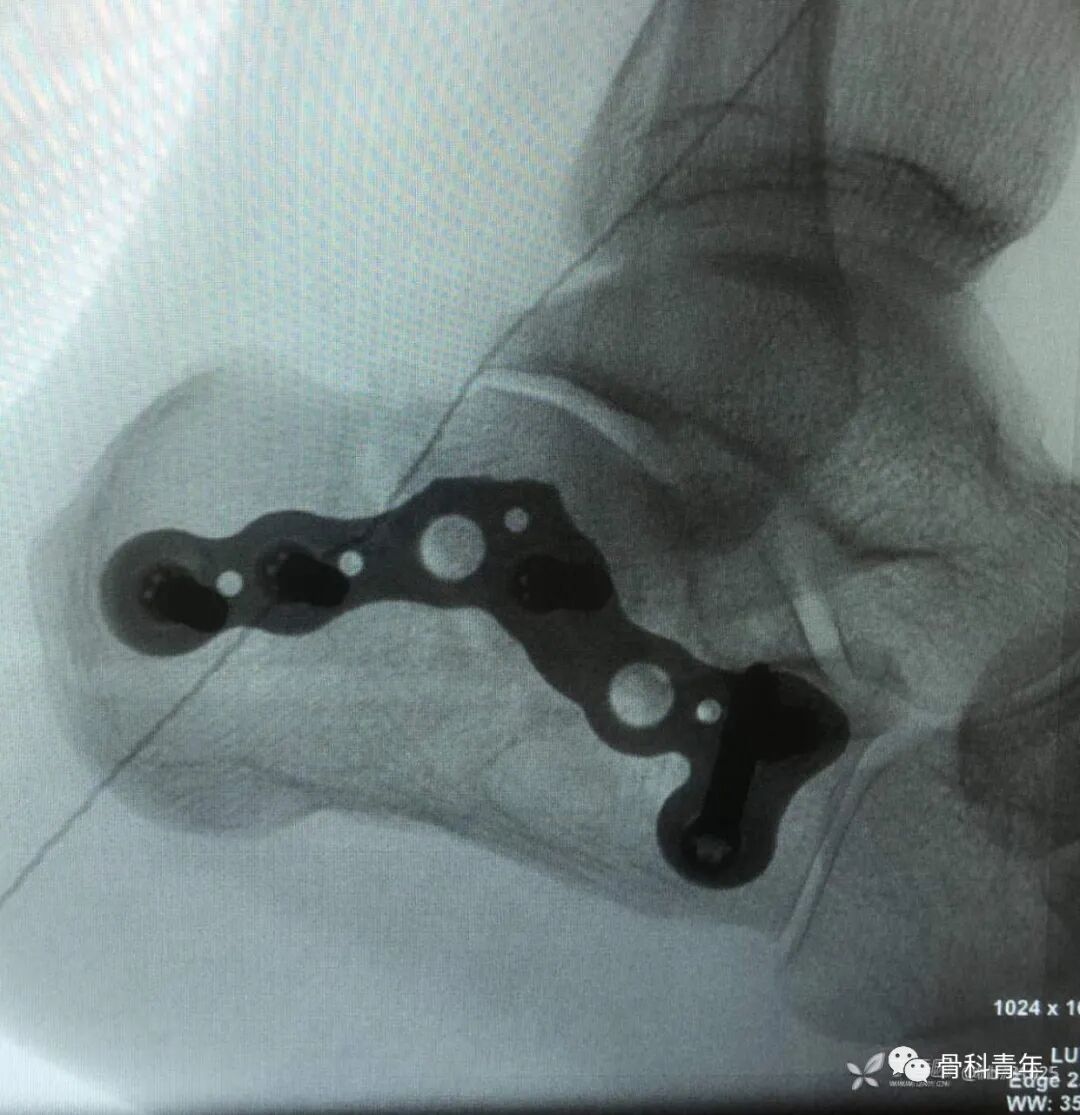

15.跟骨骨折(L入路)